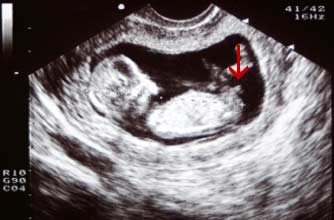

Boy nub: The nub is at a much steeper angle upwards, indicating that this baby is a boy.

小肿块以一个陡峭的角度向上指,显示这个胎儿是个男孩。